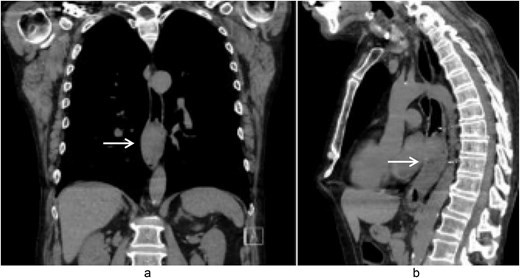

A 58-year-old male with a history of hypertension, daily alcohol use, and 35 pack year smoking history presented with progressive dysphagia and significant weight loss over a period of 3 months. His symptoms began with heartburn, with initial failure of empiric treatment for reflux. He then developed dysphagia to solids that progressed to liquids and eventually an inability to tolerate his own saliva. Over that timeframe, he also noted unintentional weight loss of ~30 lbs. He eventually presented to the emergency department where a CT scan raised concern for an obstructing esophageal mass (Fig. 1). He urgently underwent upper endoscopy revealing a large polypoid tumor with a broad base located in the lower esophagus (Fig. 2). Biopsies revealed a high-grade malignant neoplasm with spindle cell features concerning for a sarcoma. Further workup with brain MRI and positron emission tomography (PET) scan confirmed a hypermetabolic esophageal mass without evidence of distant metastatic disease (Fig. 3). Unfortunately, endoscopic ultrasound was unable to be performed given the nearly obstructive nature of the tumor.

Coronal (a) and sagittal (b) views of the initial CT scan at time of presentation that revealed a large esophageal mass with concern for complete obstruction (arrows).